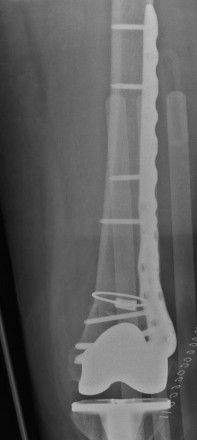

Case 2

This 73 years old female patient fell in bathroom 4 weeks after routine TKR. She sustained Lewis & Rorabeck Type 2 periprosthetic fracture of TKR.

The fracture was reduced and fixed with Zimmer cable ready cerclage cable and 9 holes distal femur NCB periprosthetic plate.

Provided by Mr Aaron Ng FRCS (Tr & Orth), Pinderfields General Hospital, Wakefield, UK.